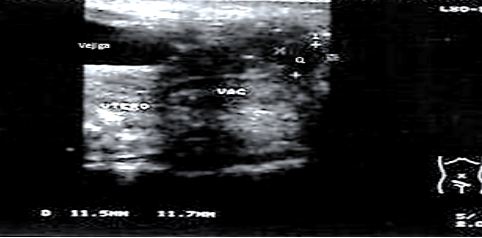

El ultrasonido abdominal resulta normal, el ultrasonido ginecológico no demuestra alteraciones uterinas descartándose la posibilidad de hidrometrocolpos; observándose hacia la región más distal una imagen ecolúcida, quística, bien circunscrita que mide 11.5 x 11.7 mm. (Figuras 1 y 2)

Fig. 1 Ultrasonido suprapúbico con transductor de 8 MZ visualizándose vejiga, vagina (vag), útero y la imagen quística distal (Q)